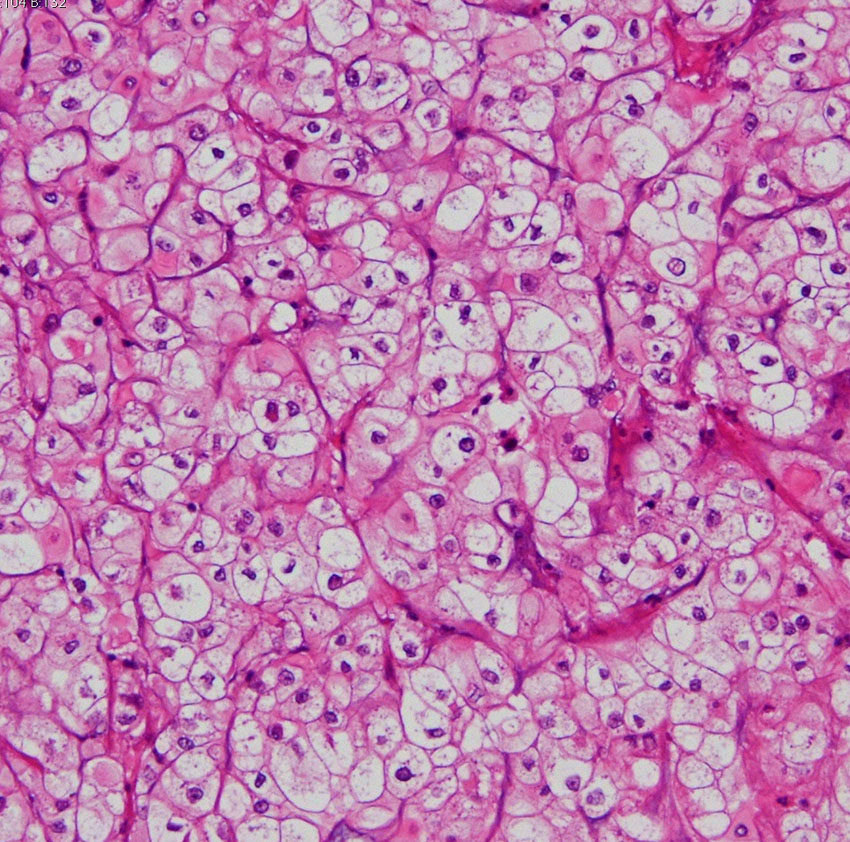

病理像です。軟骨様組織を混在しない純粋な脊索腫です。核を中心にして大きな丸い細胞体には空胞が目立ちます。空胞腫瘍細胞 physaliphorous cellsのシート状配列が特徴的です。左上の写真にわずかに粘液状間質(青く染まるところ)がみえます。